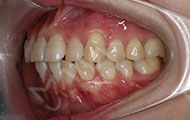

在主任的建议下拔了牙,根据我的牙齿情况,主任做了适合我的矫牙方案。选择了时代天使双膜矫治器,矫治器是透明的,可以自行摘戴,满足了我想矫正又怕丑的要求,让我在别人不知道的情况下,拥有整齐的牙齿,在矫正之前是可以在计算机上模拟显示整个矫治过程中牙齿的变化过程,可以很直观的看到,让我自己感觉心里很放心,经过一个月的等待,终于戴上了牙套,给主任和麦芽点赞!

2017-12-1不让自己留遗憾,我与歪牙要打持久战

经过朋友良心推荐,最终选择了麦芽口腔。在麦芽是张超主任给我检查的牙齿,然后跟着医助拍的片,这期间都有专人负责,张主任很专业的为我定制了方案,当天就取了牙模~